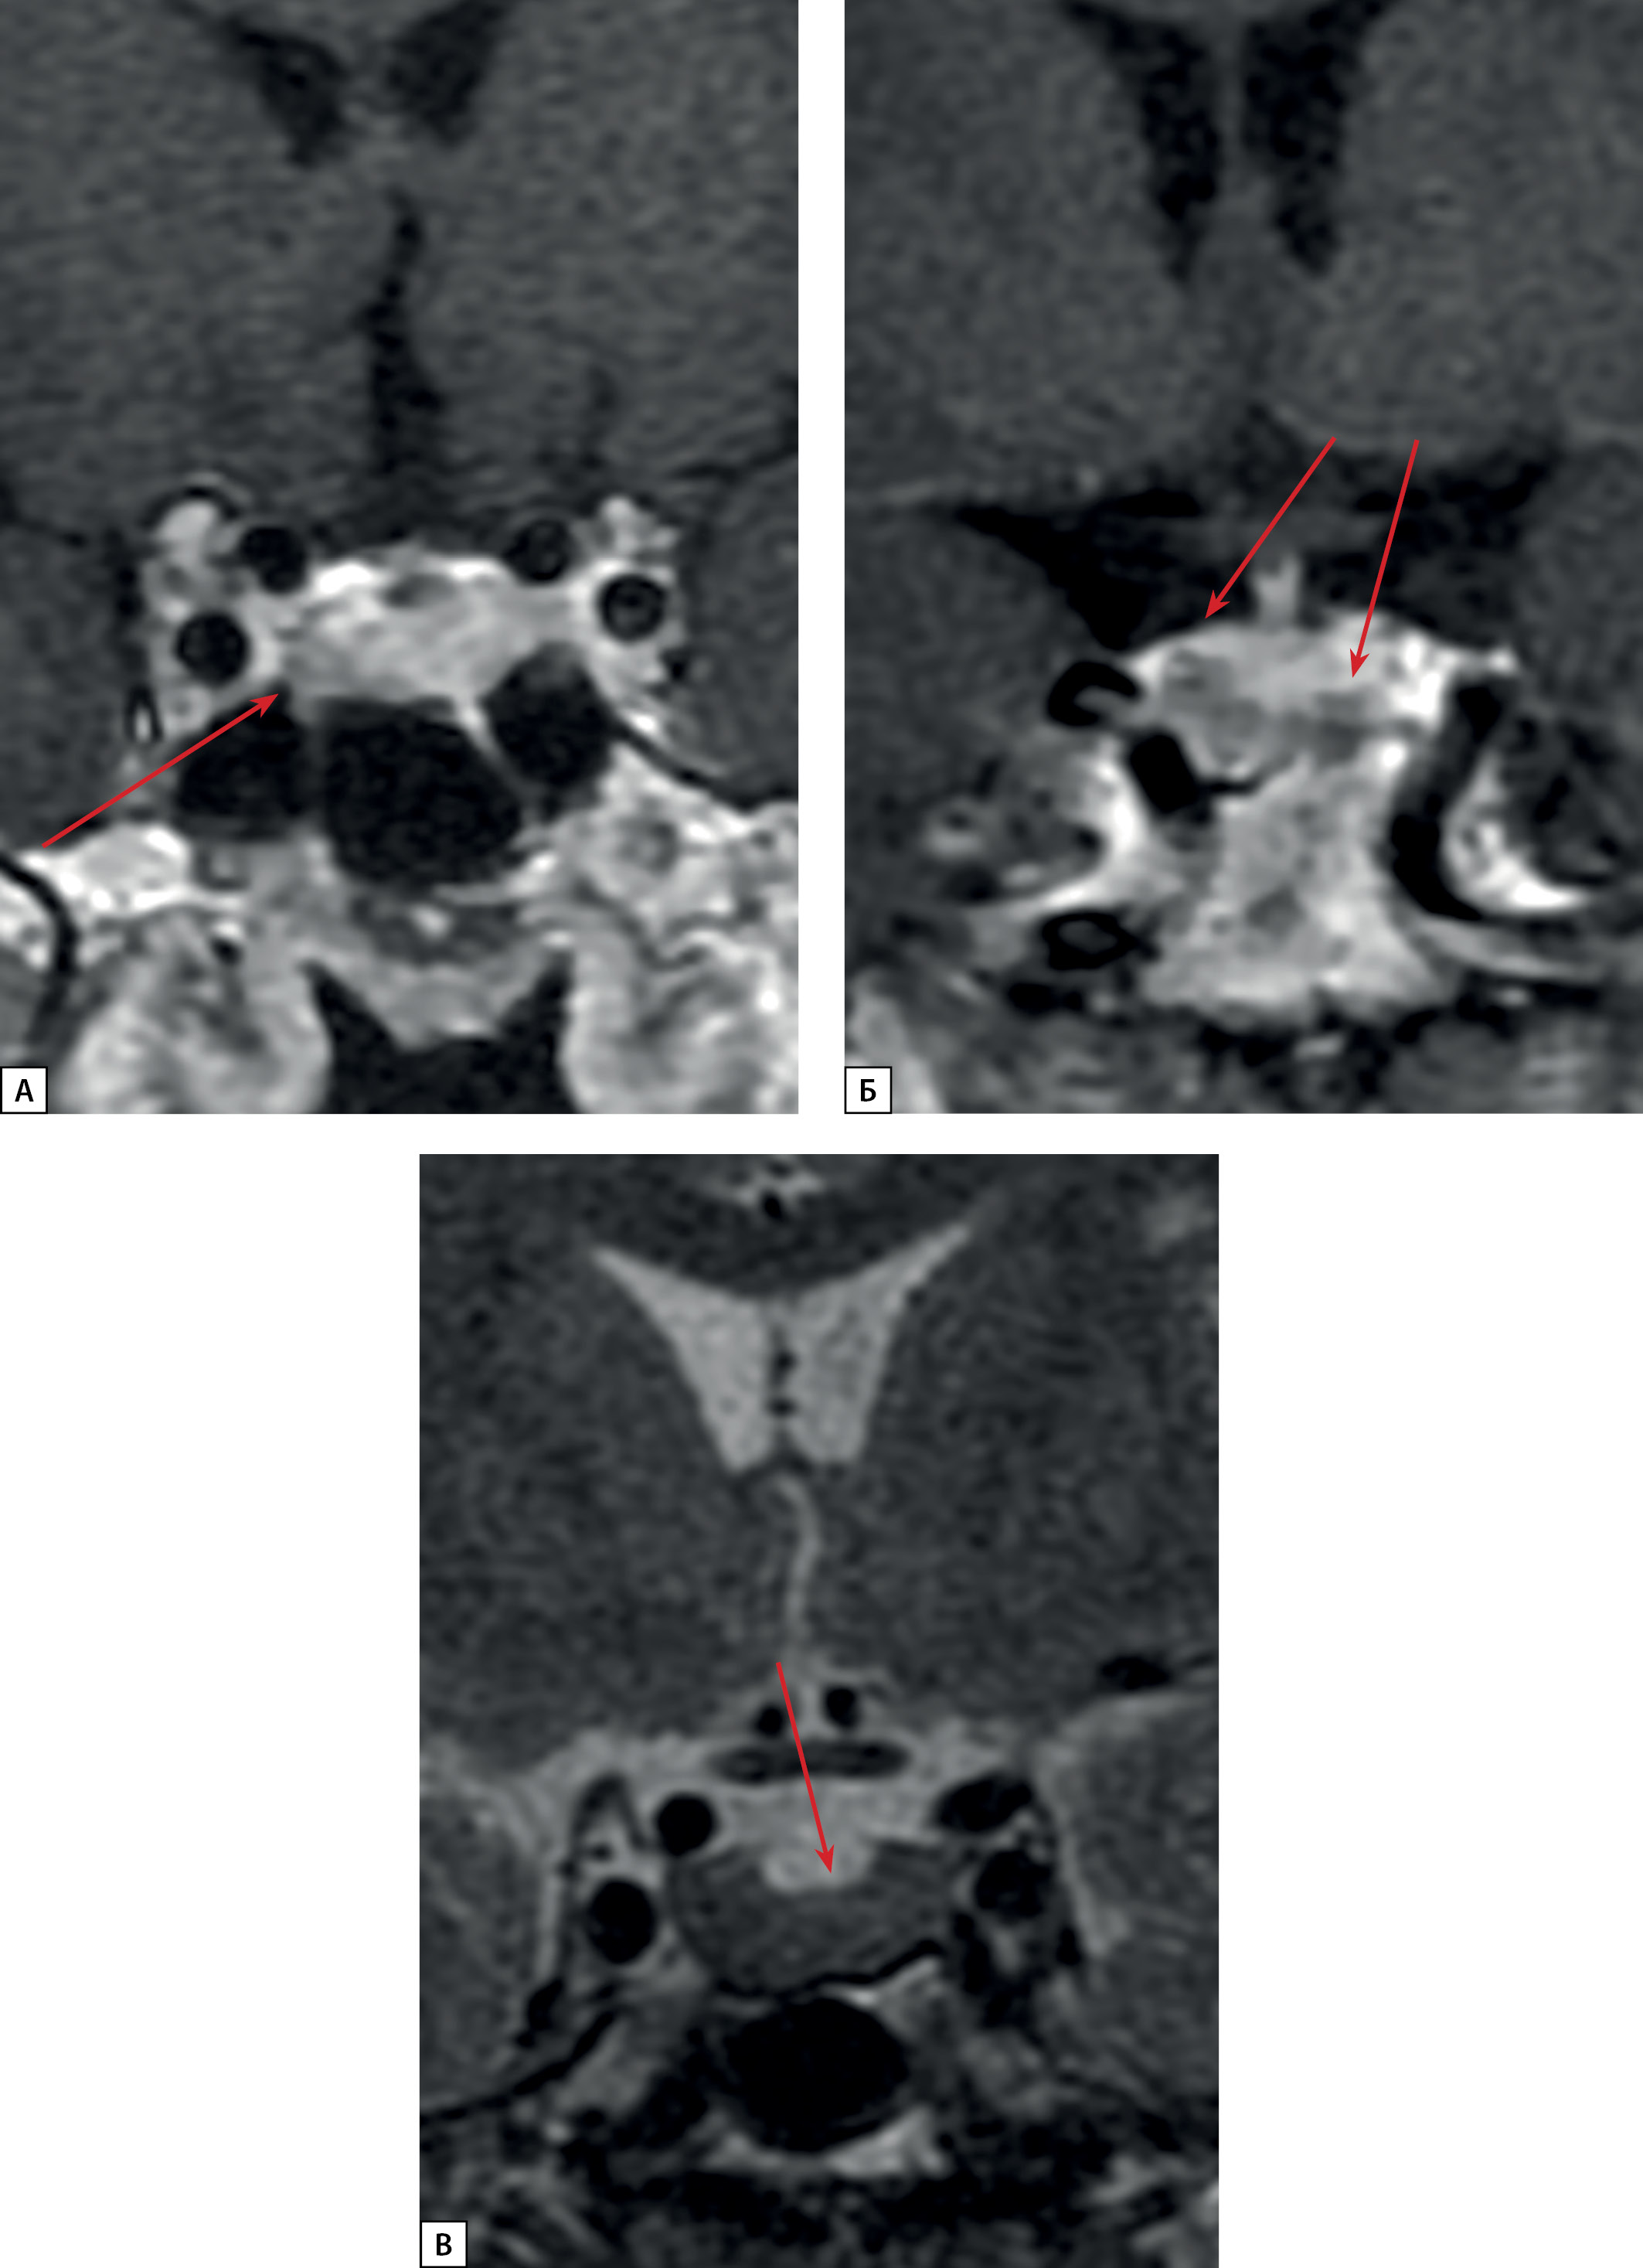

Figure 2: Patient S.N.Y. anterior pituitary cor MRI.

A: T1 WI with contrast agent. A microadenoma (see arrow) in the left anterior pituitary; B: T1 WI with contrast agent. Rathke’s cleft cyst (see arrows); C: T2 WI. A diffusely reduced MR signal on T2 WI from anterior pituitary tissue (see arrow)

A female patient D.I.E., born in 1959, was first admitted to Endocrinology Research Centre at the age of 60. Her complaints included marked general weakness, headaches, joint pain, sweating, weight loss, and facial swelling. The patient considered herself to have been unwell for the last two years, ever since an examination after the flu revealed an increase in blood glucose up to 9.3 mmol/L. Later, glycaemic parameters normalised and diet therapy was recommended. Due to general malaise, the patient visited a local endocrinologist’s practice, and the examination revealed an increase in IGF-1 level up to 349 ng/ml (normal up to 200). Brain MRI showed marked irregularity of the anterior pituitary structure on the left side; thus, a pituitary adenoma could not be excluded. In the middle part of the pituitary, a T2 WI hyperintense structure was observed (3.8×1.5 mm), which did not absorb contrast agent (Rathke’s cleft cyst). The MR signal from the anterior pituitary was slightly reduced on T2 WI (Figure 4 a, b).

Figure 4: Patient D.I.E. MRI and CT scans.

A: anterior pituitary cor MRI, T1 WI with contrast agent. Rathke’s cleft cyst (see arrow). An area of slightly reduced contrast agent absorption in the left side of anterior pituitary (see long arrow); B: Rathke’s cleft cyst (see arrow). Diffusely reduced MR signal on T2 WI from anterior pituitary tissue; C: lung MSCT; pulmonary mode, native phase, axial projection. A neuroendocrine tumour in S10 of the left lung (see short arrow); D: lung MSCT; pulmonary mode, native phase, axial projection. A lesion in S3 of the left lung with intra- and peribronchial spreading – a seeding site (bold arrow).